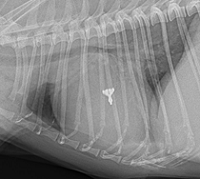

• Patent ductus arteriosus (PDA): This is the most common congenital cardiovascular abnormality in dogs. Cavaliers have been shown to have a "high prevalence" for PDA. It occurs when a temporary blood vessel -- the arterial canal -- which is used to bypass the fetus's undeveloped lungs in the womb and allows blood to pass from the right side of the heart to the left, fails to seal within a week after birth. Normally, this vessel will begin to seal once the puppy begins breathing. PDA compromises the circulation of blood through the heart. It is believed to be inherited as a polygenic threshold trait with a high rate of heritability in some breeds and is considered to be hereditary in the CKCS. Read more details about this disorder here.